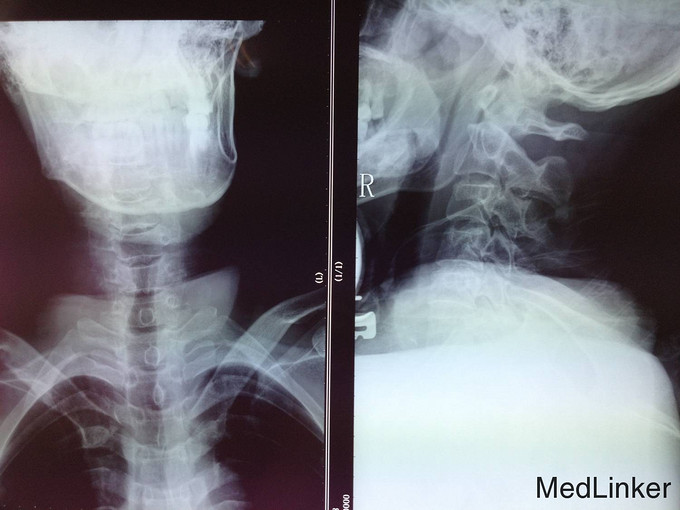

患者于2014-06-18日16:00点左右从3米处坠落,前胸着地,致颈部疼痛,四肢活动受限,受伤后被家人送入当地医院,行X线检查,颈椎MR检查,提示为颈椎损伤。患者及家属为求系统治疗,急来我院;急诊以“颈椎外伤”为主诊断收入我科。病来患者一般状态无头晕及头痛,无咳嗽咳痰,无恶心及呕吐 ,饮食可,留置导尿,大便未排,近期体重无明显改变。

诊断:颈椎外伤(不全瘫);脊髓损伤 患者入院后完善相关检查,查无手术禁忌症后急诊行颈椎后路椎板减压椎管扩大单开门侧块螺钉内固定术,术后患者生命体征平稳,双上肢感觉疼痛,双下肢足趾肌力恢复到1级,术后3天后转入康复科继续康复治疗。